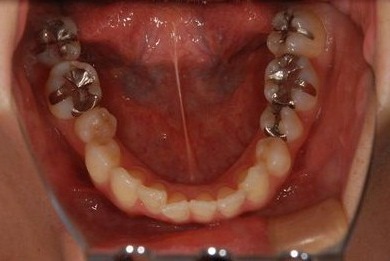

| 性別/年齢 | 女性 / 31歳 | ||||||||||||||||||||||||||||||||

| 主訴 | 前歯の歯茎が黒ずんでいるので、改善したい。 | ||||||||||||||||||||||||||||||||

| 治療方針 | 上顎前歯、メタルボンドセラミッククラウンからオールセラミッククラウンにする事で、審美的回復を行う。 | ||||||||||||||||||||||||||||||||

| 治療内容 | CAD/CAMオールセラミッククラウン2本(セラミック用土台2本) | ||||||||||||||||||||||||||||||||

| 総治療費 | 142,800円 | ||||||||||||||||||||||||||||||||

| 治療期間 | 2ヶ月 |